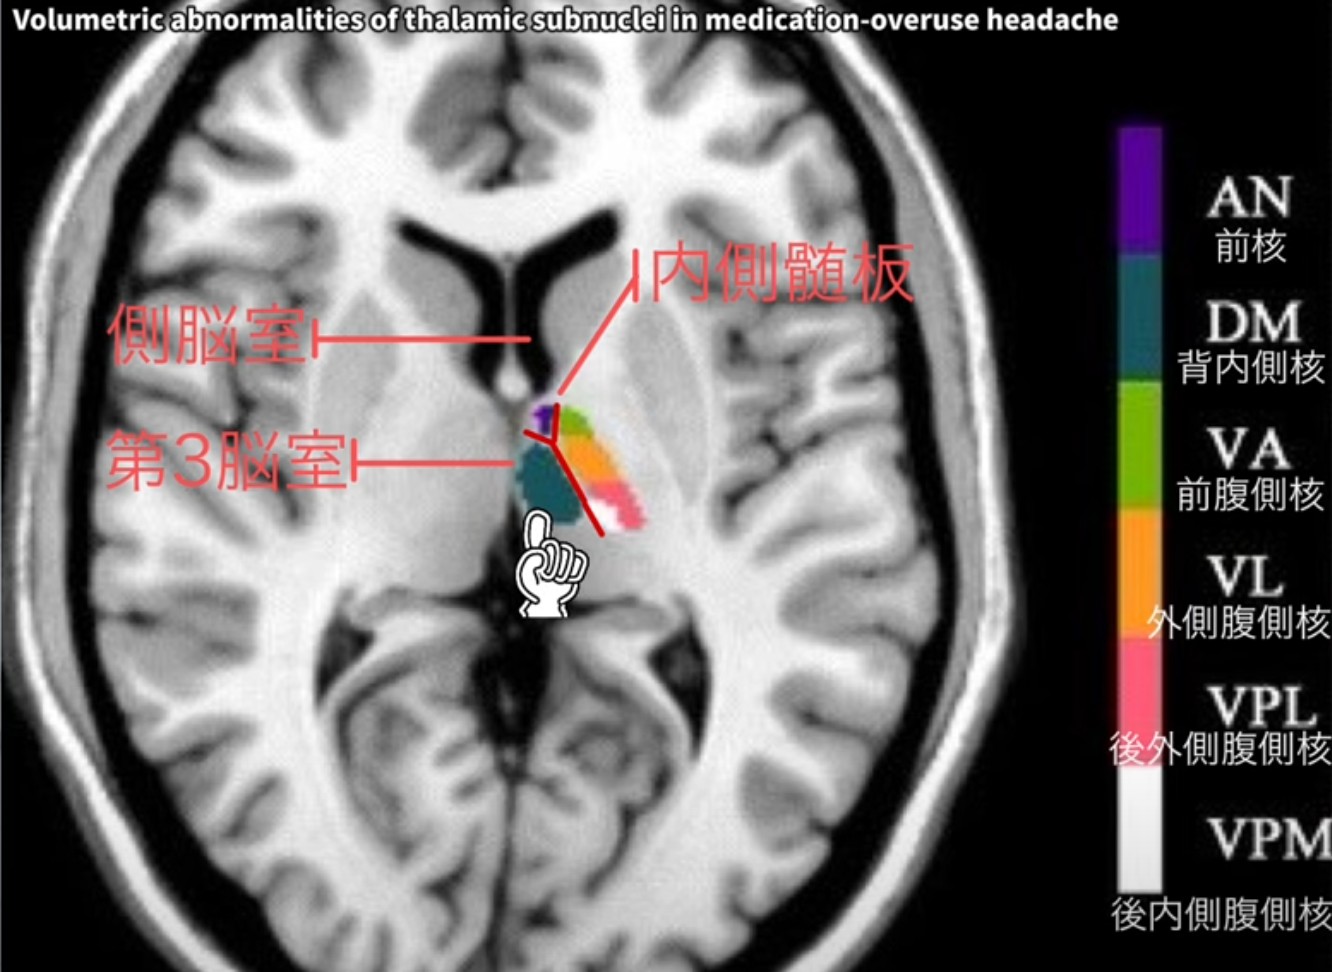

視床背内側核(MD核)とは?

⑧MRI と背内側核: 標準的な MRI で背内側核を視覚化するのはなぜ難しいのですか?また、その接続性と機能についてのより詳しい洞察を提供できる技術は何ですか?

⑧MRI と背内側核: 背内側核は、解像度の制限があるため、標準的な MRI では視覚化することが困難ですが、DTI や fMRI などの高度な技術を使用すると、その接続性と機能についてより多くの洞察を得ることができます。